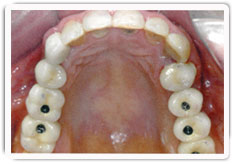

Screw-retained – instead of being glued, the artificial teeth are held onto the underlying abutments by screws. This requires openings (figure 20) to be made at the top of the artificial teeth for the screws to pass through. These holes are not visible when you smile as they are sealed with tooth-coloured filling material.

Figure 20: Screw-retained crowns with access holes before being sealed with tooth- coloured fillings |